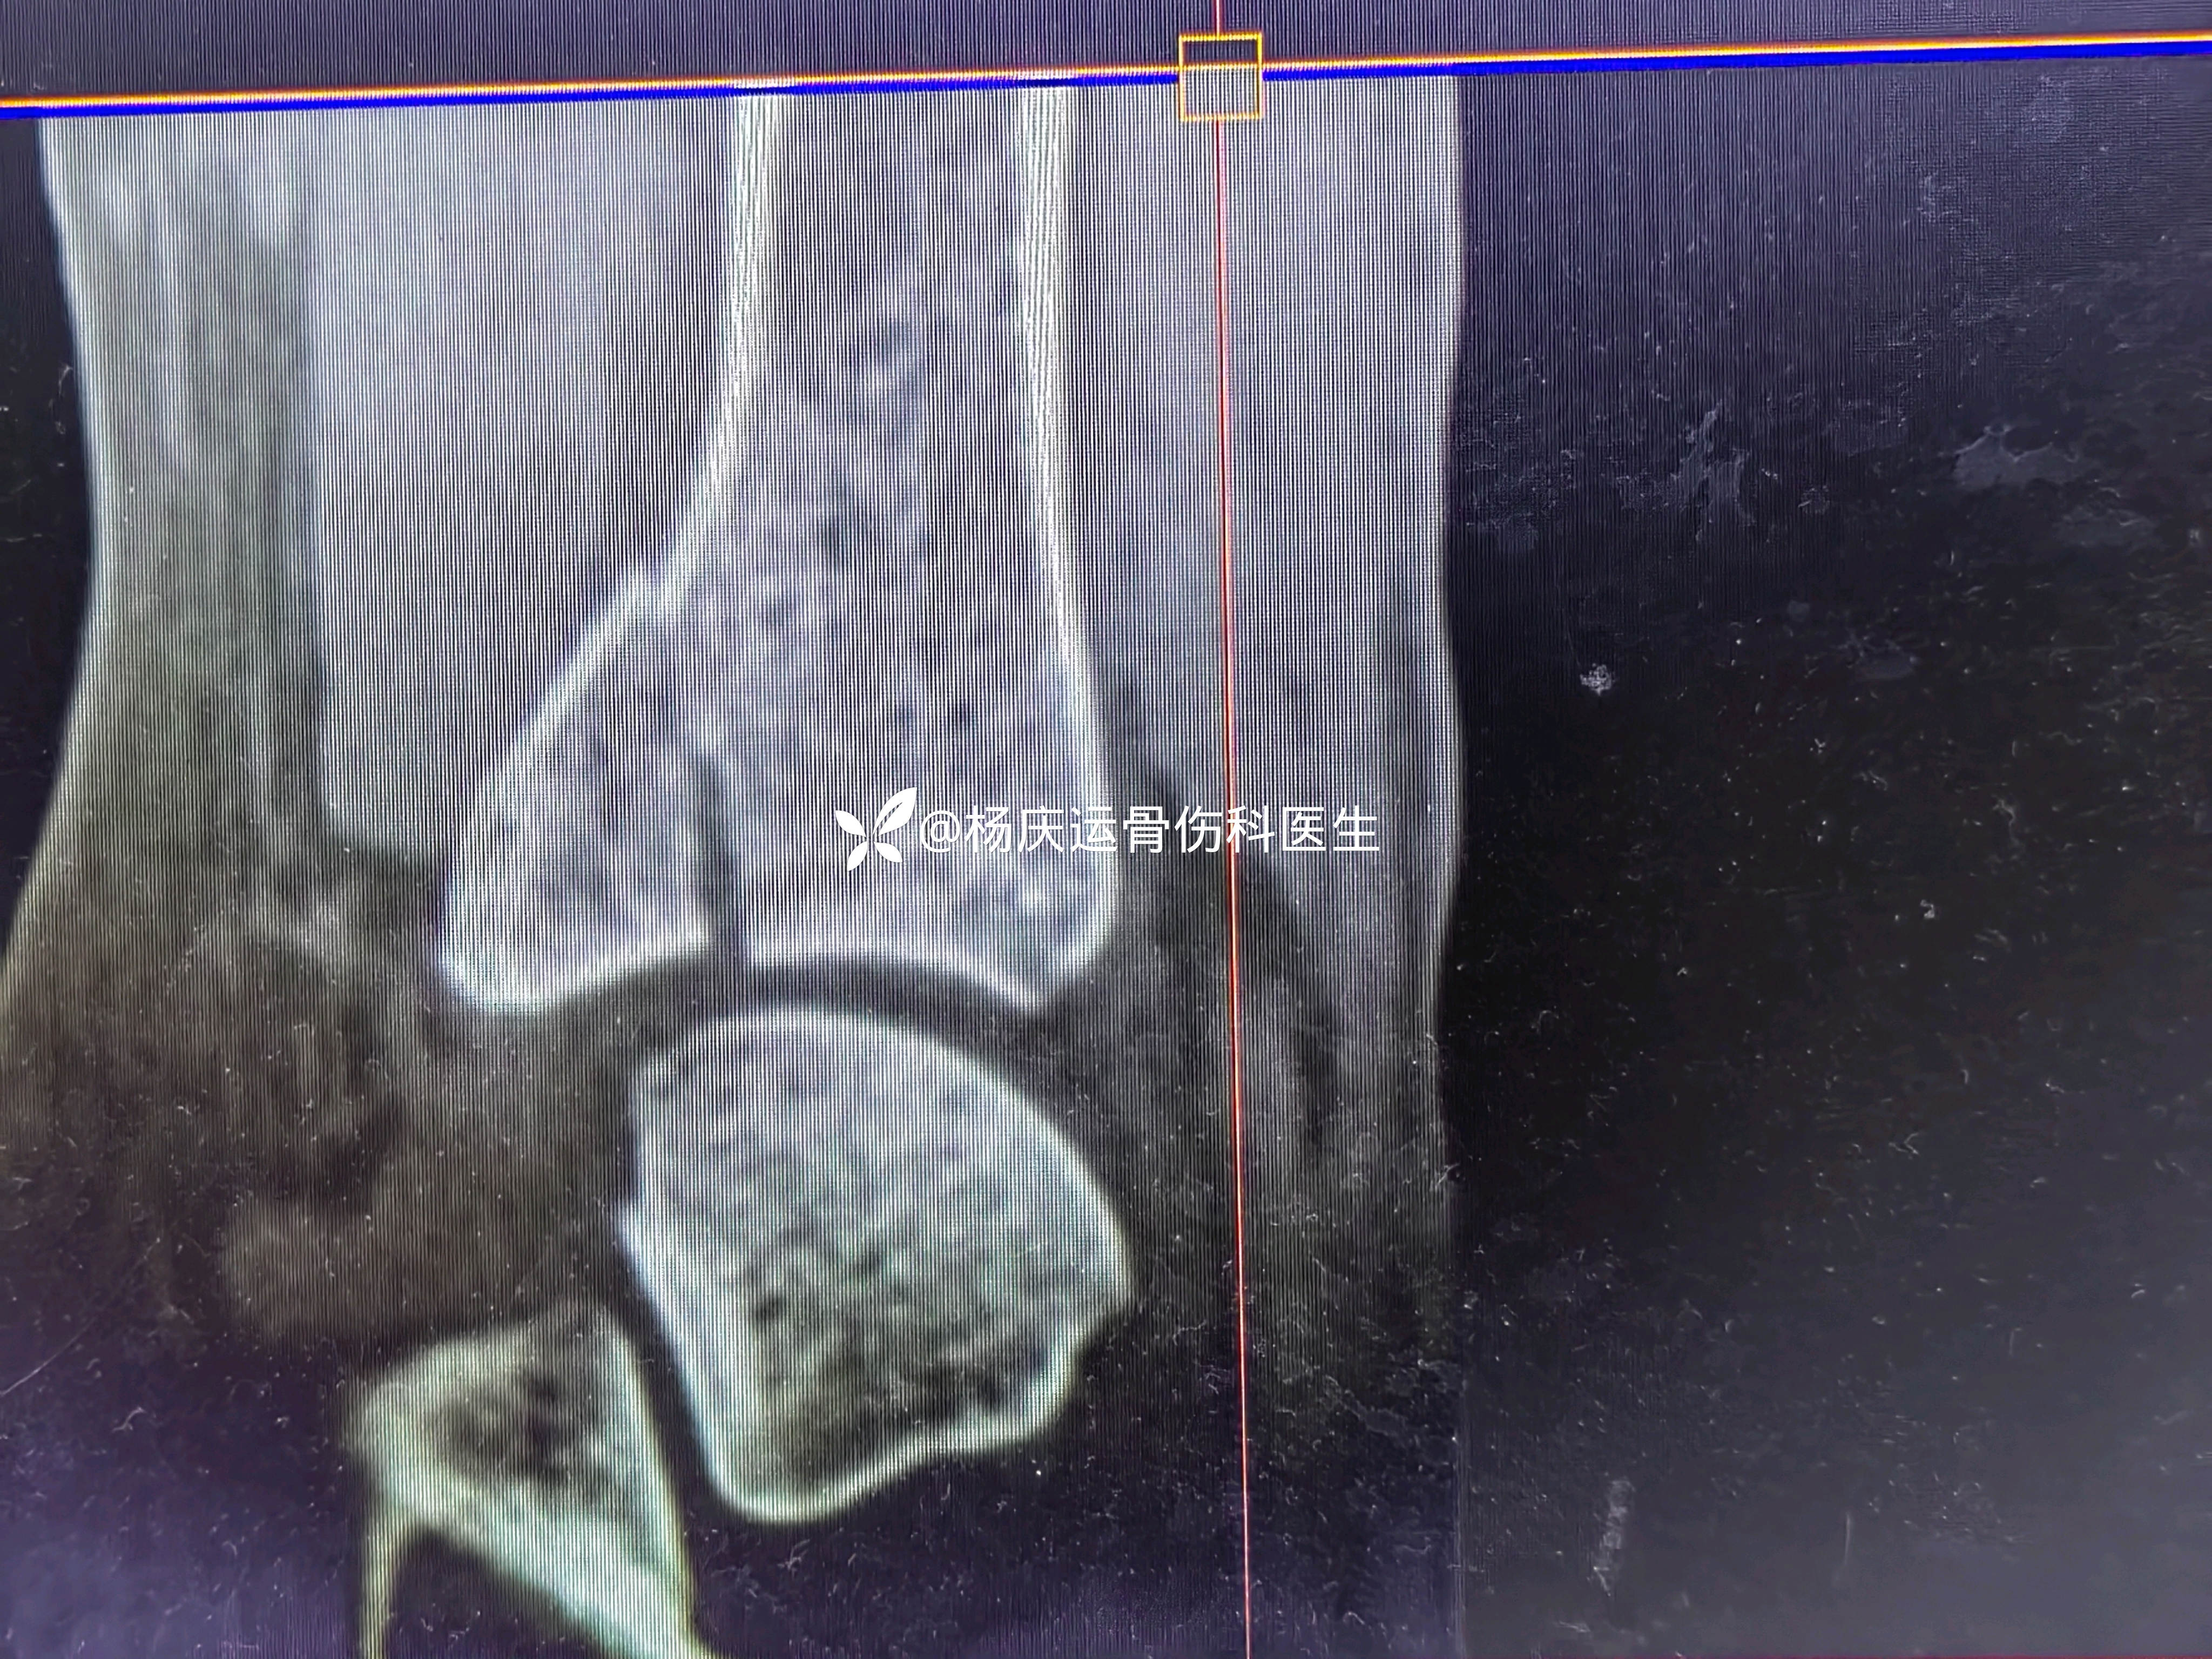

3天复查CT

关节面台阶约1.0mm